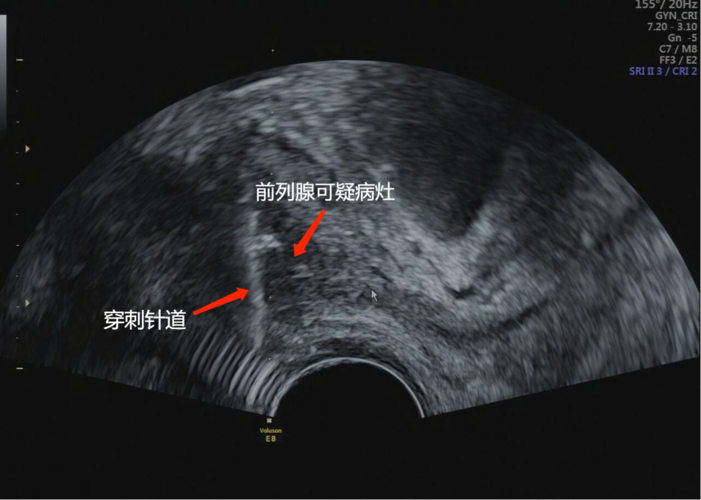

我科常规开展无痛经直肠超声引导下前列腺精准穿刺活检无痛化精准化